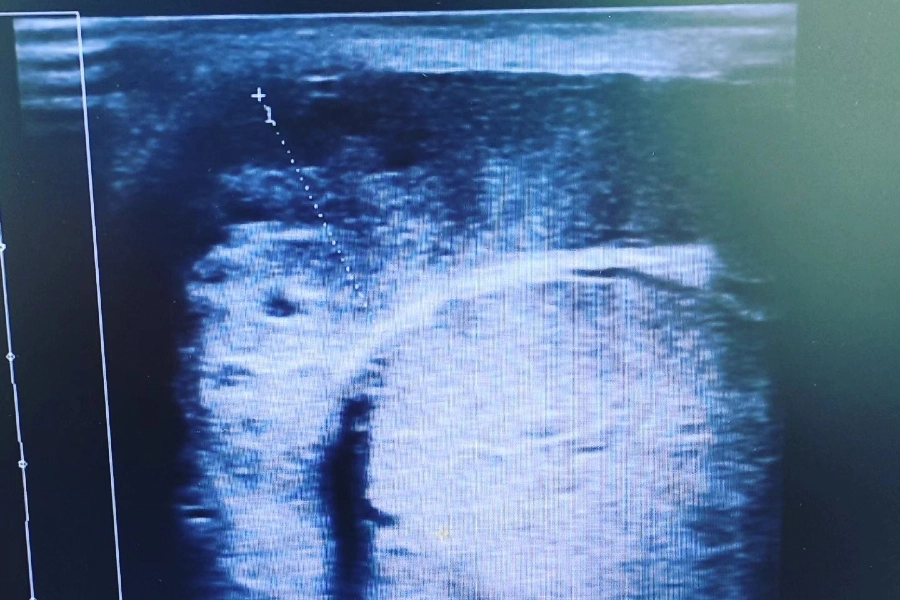

Ο Καμπούρης Ιωάννης είναι Κτηνίατρος και διατηρεί ιδιωτικό κτηνιατρείο στην Καλλιθέα. Είναι απόφοιτος της Κτηνιατρικής Σχολής. Στον χώρο του κτηνιατρείου του, παρέχονται ολοκληρωμένες κτηνιατρικές υπηρεσίες για τους μικρούς φίλους, με έμφαση στη φροντίδα, την πρόληψη και τη θεραπεία. Πραγματοποιούνται χειρουργικές επεμβάσεις, ακτινογραφίες, ενδοσκοπήσεις, καθώς και υπερηχοτομογραφικές αναλύσεις για την ακριβή διάγνωση παθολογικών προβλημάτων. Επιπλέον, παρέχονται εμβολιασμοί, ηλεκτρονική σήμανση (microchip), οδοντιατρικές πράξεις, καθώς και εργαστηριακές εξετάσεις αίματος και ούρων, με στόχο την πλήρη και υπεύθυνη φροντίδα κάθε κατοικιδίου. Το κτηνιατρείο καλύπτει υπεύθυνα κάθε ανάγκη φροντίδας των ζώων συντροφιάς, προσφέροντας υπηρεσίες με συνέπεια, επιστημονική γνώση και σεβασμό απέναντι στους μικρούς ασθενείς.